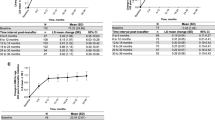

The data for all remaining clinical outcomes are presented as scatter plots along with the predicted modelled change in clinical outcomes over the study period in Fig. 4. The change over time in clinical outcomes is expressed as an annualised slope, which is interpreted as the predicted annual change in the outcome. Acceptable LCI measurements were collected on 28 (39.4%) participants at baseline. The mean annual change from baseline in LCI2.5 (annualised slope − 0.055 (95%CI -0.61 to 0.50), p = 0.85) measurements among participants were not significant. Regarding secondary clinical outcomes on the 71 participants, there was a significant change over time in BMI z-scores (0.09 (0.03 to 0.15), p = 0.005), weight z-scores (0.1 (0.06 to 0.15, p < 0.0001) and height z-scores (0.05 (0.02 to 0.09), p = 0.002) among participants. The mean annual change from baseline in ppFEV1 (-2.45 (-4.44 to 2.54), p = 0.66) measurements among participants was not significant.

The data for all remaining clinical outcomes (LCI2.5, ppFEV1, weight z-score, height z-score, BMI z-score) are presented as scatter plots along with the predicted modelled change in clinical outcomes over the study period. The change over time in clinical outcomes is expressed as an annualised slope, which is interpreted as the predicted annual change in the outcome. Study day was defined as the number of days pre/post initiation of LUM/IVA therapy